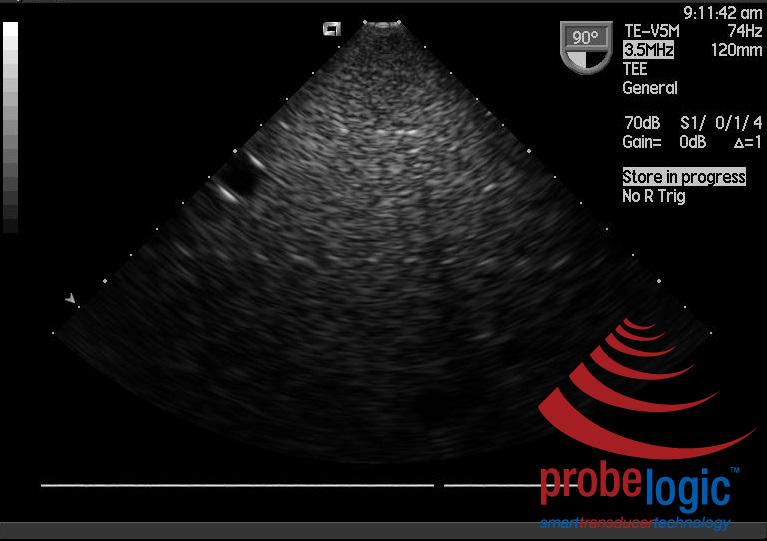

Now if we compare a good V5Ms ultrasound image from the same phantom on the same ultrasound system. Firstly the good image, you can see how clear the phantom dots throughout the image are: